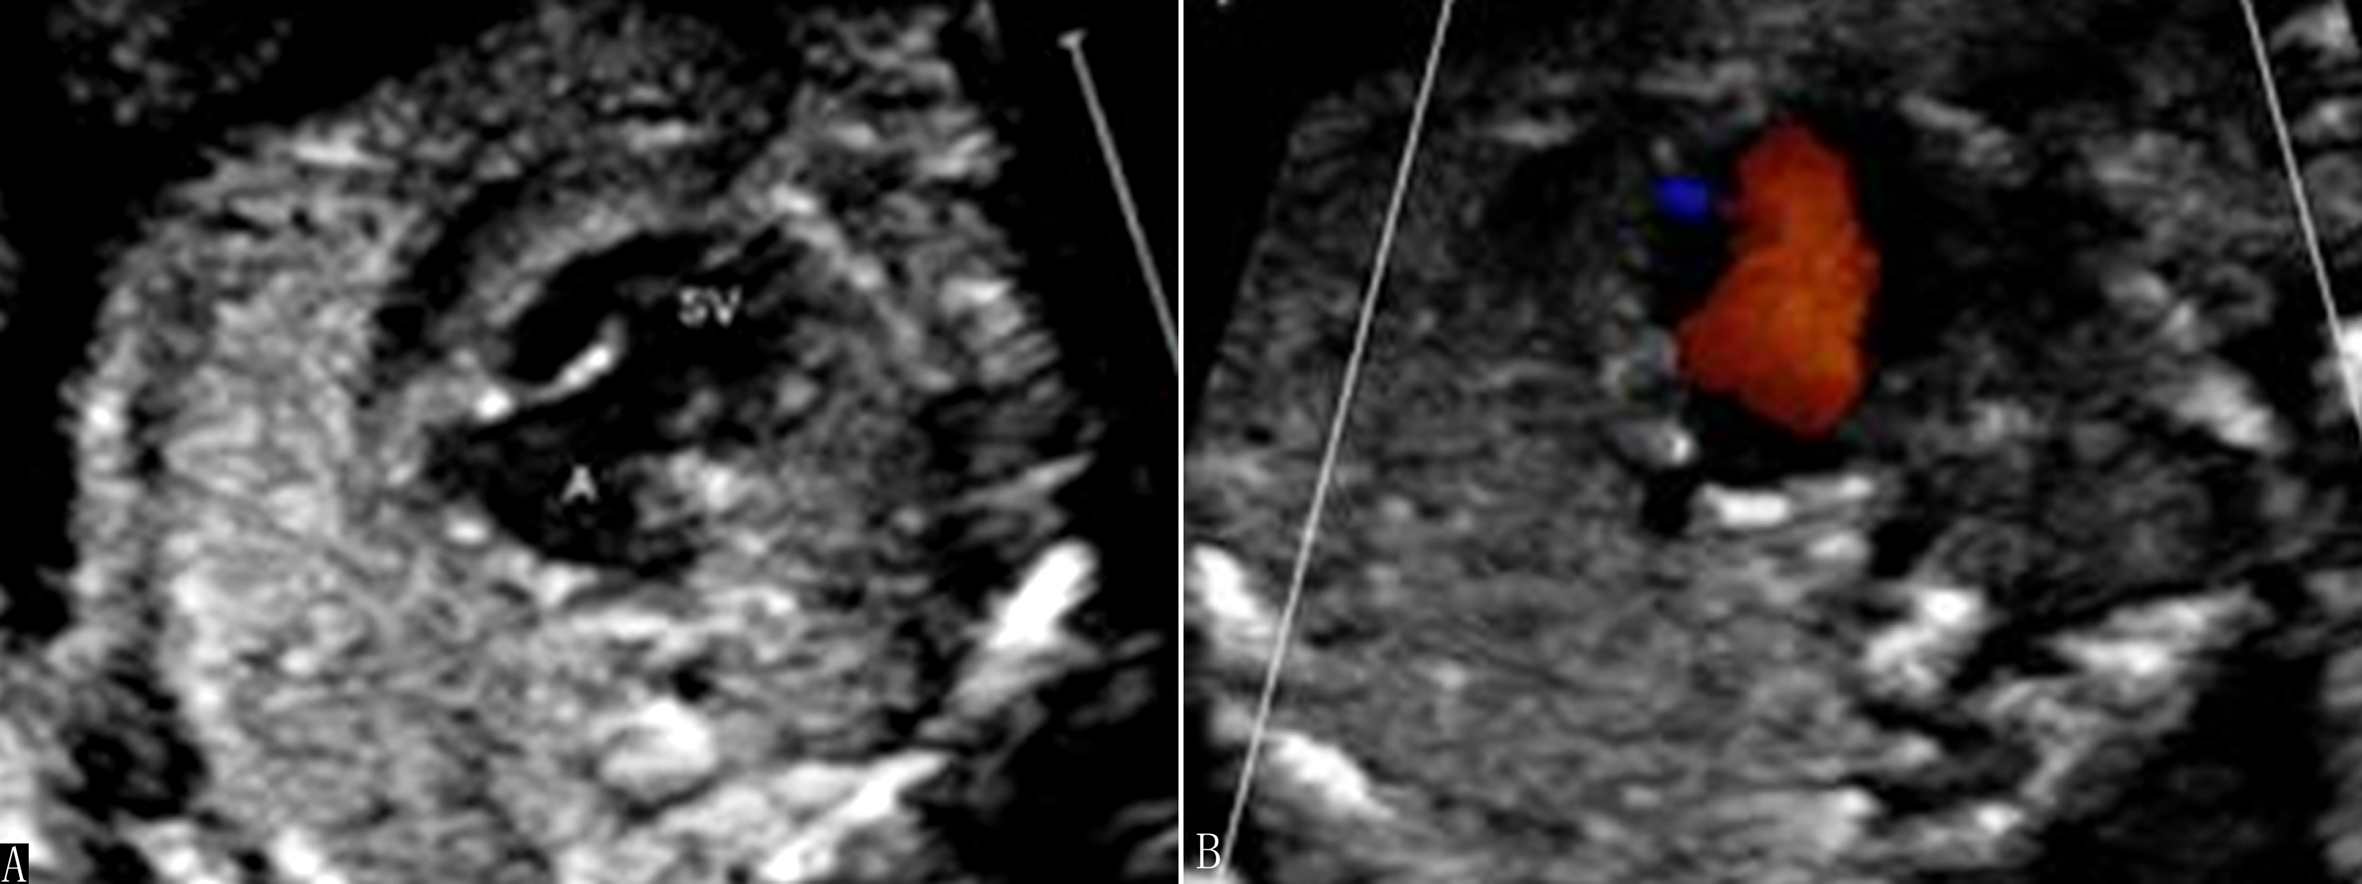

2. 超声诊断要点 二维超声显示左、右心室不对称,左心室明显小于右心室,心轴明显左偏;如伴有二尖瓣闭锁,则左心室内可不显示彩色多普勒血流信号(图1)。彩色多普勒超声检查三血管气管切面主动脉弓与动脉导管血流方向不一致,主动脉弓血流不是流向降主动脉,而是由动脉导管反流而来(图2)。

图1 胎儿左心发育不良综合征:LV<RV,心轴明显左偏